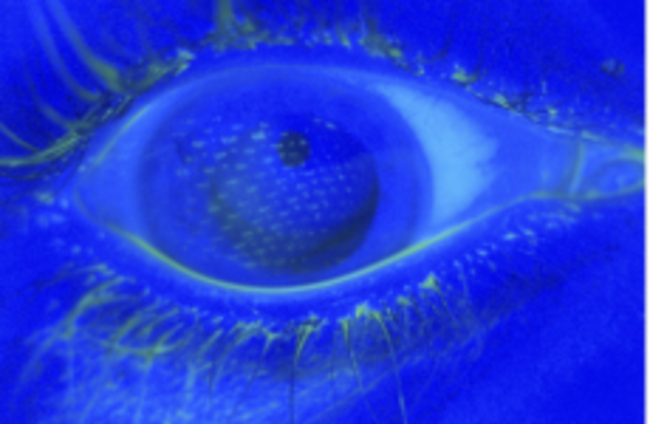

The imprint from the airbag can be clearly seen on the eyeball New England Journal of Medicine

Look closely. Can you see the imprint ?

Over her right eye, they could see the imprint of the nylon mesh pattern of the airbag cover on her cornea, while her left eye had a slight tear in the surface. In other words: the airbag had deployed so quickly that she didn’t even have time to close her eyes.